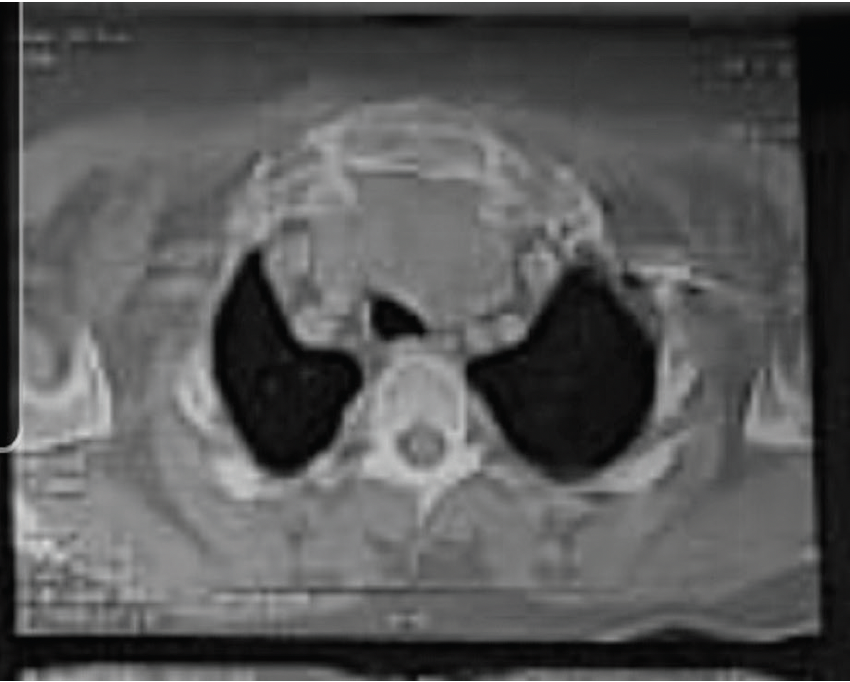

Es asintomático entre el 20–30%. Su diagnóstico se hace por pruebas de imagen; su Gold estándar es la tomografía axial computarizada.

Se detalla el caso de una paciente de 59 años de edad, quien, con síntomas opresivos esternales, a quien se le diagnostica masa mediastínica, la cual se resuelve con indicación quirúrgica, siendo resolutiva para la paciente, con mejoras en la sintomatología y diagnostico de benignidad.